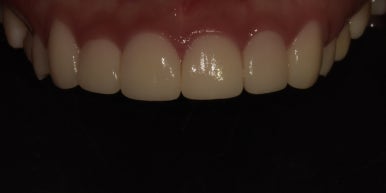

12전치 라미네이트, 크라운 치료 후

2023-07-05

1주일 후 최종적으로 보철물 제작이 완료되어 부착까지 진행해드렸는데요.

바뀐 모습 어떠신가요? 정말 몰라볼 정도로 확연하게 개선이 되었죠?

12전치 라미네이트, 크라운 치료 전후 비교

(전) 2023-06-23 (후) 2023-07-05

특히 오른쪽 아래 #42 치아는 기울어져 있던 치아가 반듯하게 개선되어 훨씬 고르게 변했고,

주변 치아와 조화가 잘 이루어지는 모습입니다.